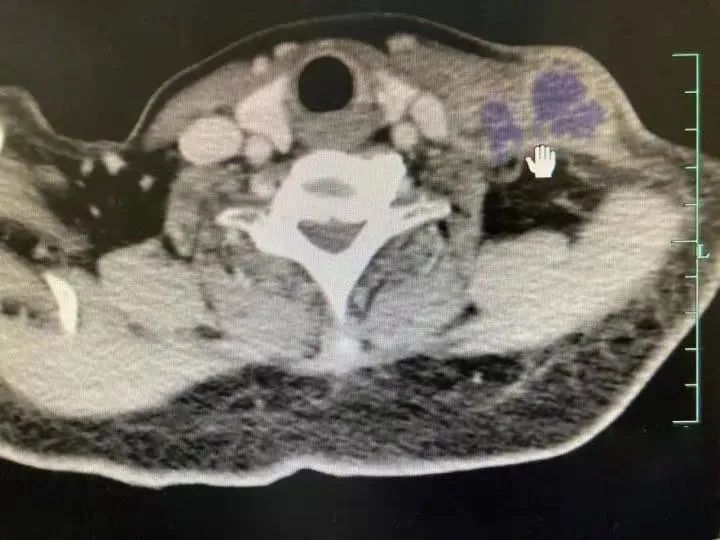

随后,陈阿姨前往杭州市红十字会医院就诊,医生为她进行了全面的病原基因检测,最终在淋巴结穿刺组织的NGS检测中发现了汉赛巴尔通体,再结合陈阿姨养猫的情况,考虑是猫抓病。

陈阿姨的CT报告结果(图源:浙医在线)